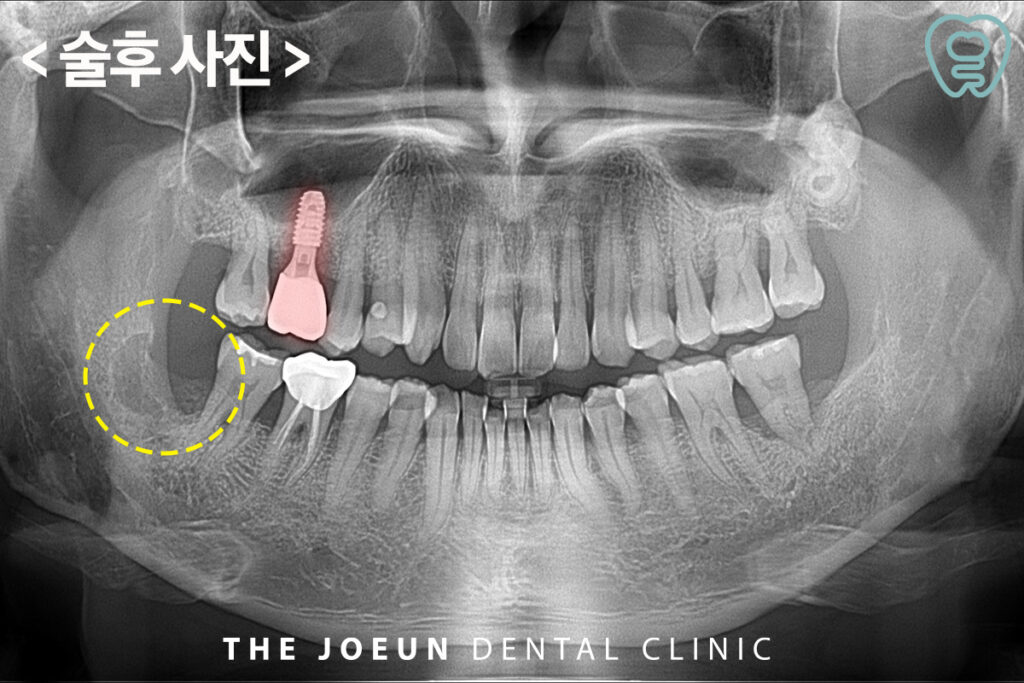

사랑니 발치와 난이도가 높은 커다란 낭종 제거까지 안정적으로 마친 후 모습입니다.

이후, 잇몸뼈가 부족한 부분을 보충하여 충분한 기간을 기다려준 뒤 임플란트 식립과 최종 보철물까지 완료하였습니다.